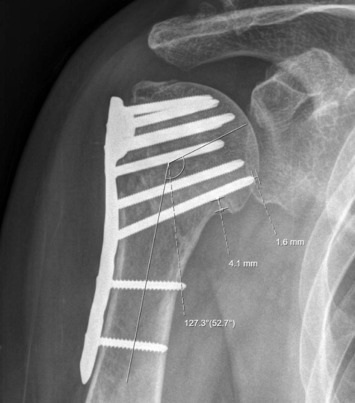

Figure A demonstrates ORIF of a left proximal humerus fracture and Figure B demonstrates fixation failure and varus collapse. Illustration A depicts an example of the trajectory of a calcar screw. Illustration B demonstrates an AP radiograph of an adequately reduced right proximal humerus fracture after ORIF with a neck-shaft angle of 127.3°, calcar distance of 4.1 mm, and distance from the tip of the calcar screw to the humeral head of 1.6 mm.

A 42-year-old male sustains a left proximal humerus fracture secondary to a motor vehicle collision. He subsequently undergoes open reduction and internal fixation, as demonstrated in Figure A. Six months later, he presents to the clinic for evaluation of continued left shoulder pain. A plain radiograph today is demonstrated in Figure B. Failure to optimize the location of a screw in what quadrant of the proximal humerus has been shown to increase the risk of developing this complication?

This patient underwent ORIF of his proximal humerus fracture and subsequently developed varus collapse. It has been shown that optimizing the location of the calcar screws within the inferomedial quadrant of the proximal humerus helps prevent the risk of varus collapse fixation failure.